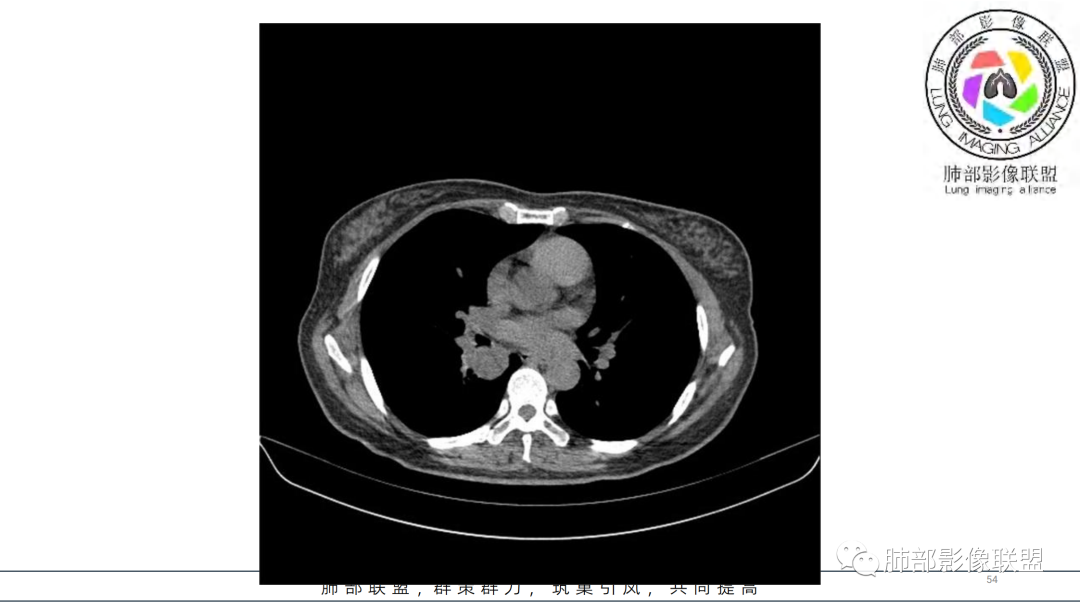

2.右肺下叶及中间段支气管后方类圆形块影,边界较清楚,未见分叶及毛刺,病灶部分突入支气管腔内(冰山一角),局部管腔狭窄,相应肺叶未见片影或体积变化。

3.块影密度均匀,未见液化坏死及钙化,渐进性强化,强化显著。

4.双肺门及纵隔未见增大淋巴结。未见胸腔积液。

中青年女性,支气管管腔内外肿块(“冰山征”),边界较清楚,强化显著,未见阻塞性肺不张,尽管未出现“类癌综合征”临床表现,仍然符合典型类癌影像学表现。